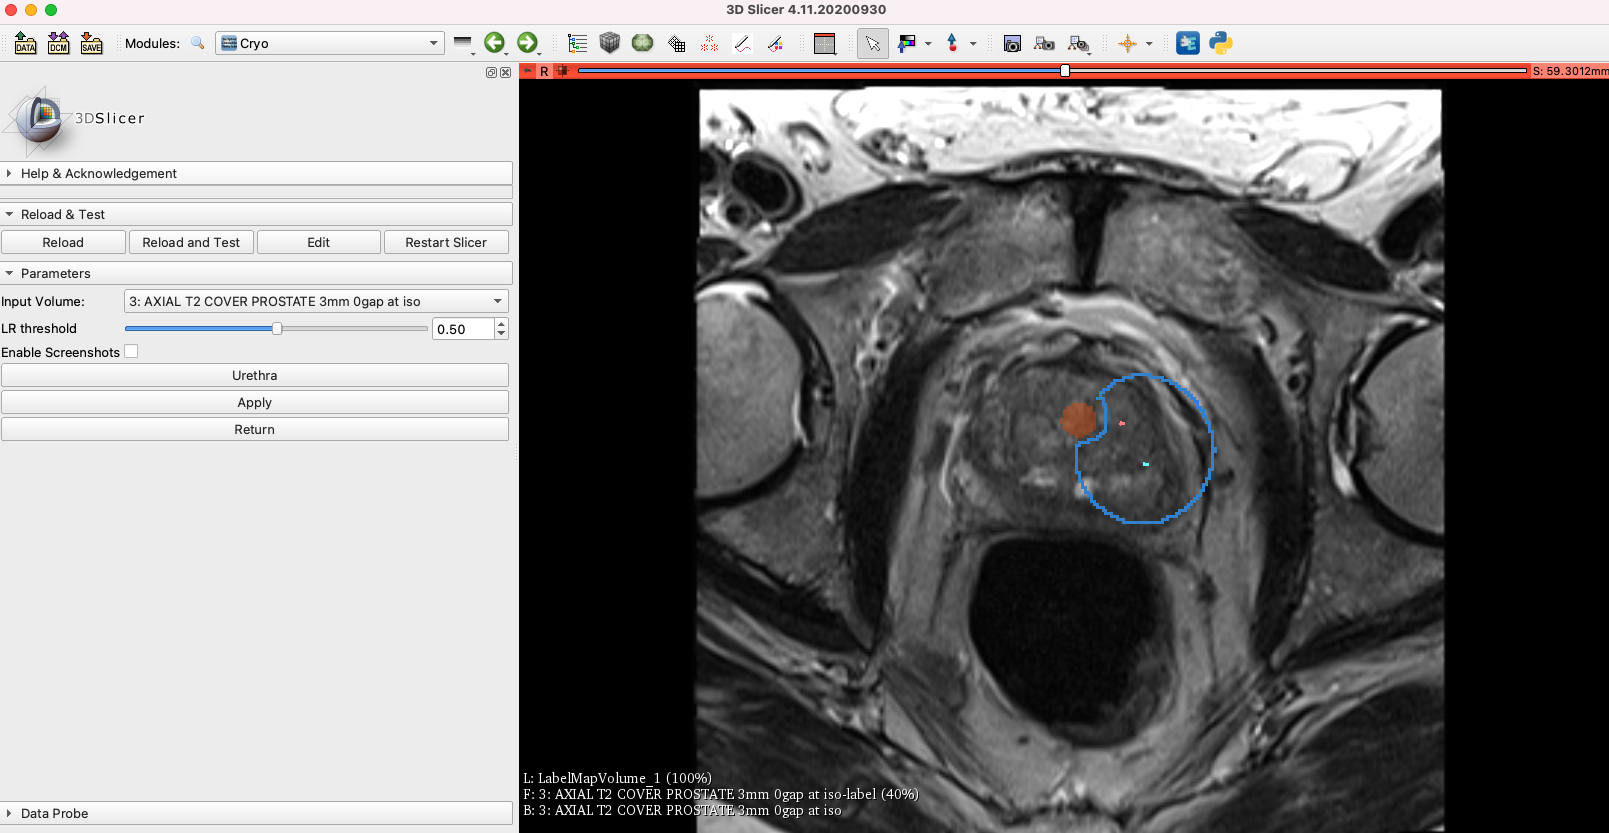

We’ve developed a module this week that capture the desired probe location defined by the physician on the ProstateAblation module, a few points along the urethra, and uses the logistic regression presented on CARS2020 [1] to estimate the final iceball. The user can also define the threshold to select the sensitivity of the logistic regression. The code is still quite slow as it goes through the entire image, future implementation should use a ROI around the probe location. We are also working on displaying the total volume of the iceball and the minimum ablation margin. According to the literature, an ablation margin around 5mm is desirable.

Figure 2: The blue segmentation is the estimated iceball given the probe location and the segmented urethra.